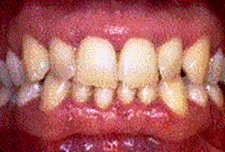

Parodontite moderate

dintii par alungiti datorita retractiei gingivale

pot apare abcese parodontale

halena

mobilitate dentara si diastemizare patologica

pungi parodontale de 4-6 mm

resorbtie osoasa